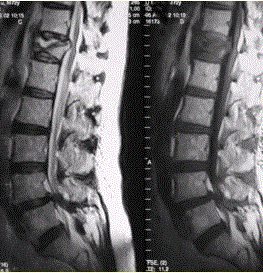

患者男,70岁,因肝癌入院,准备行肝移植手术。住院期间因腰扭伤而腰痛,故行腰椎MRI检查(如下图)。㎝鉴别椎体良、恶性压缩性骨折,支持良性病变的征象有...

问题 患者男,70岁,因肝癌入院,准备行肝移植手术。住院期间因腰扭伤而腰痛,故行腰椎MRI检查(如下图)。 ㎝鉴别椎体良、恶性压缩性骨折,支持良性病变的征象有

选项 A.椎体前后径加长 B.椎体后缘弧形后凸 C.椎体内较均匀信号异常 D.椎体后缘平直 E.椎体后上角后翘 F.椎体内可见长T1长T2液体信号影 G.DWI序列椎体呈低信号 H.DWI序列椎体呈高信号

答案 DEFG

解析 DEFG